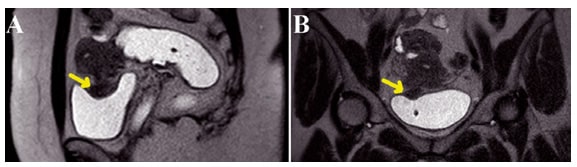

Abaixo vemos 2 ressonâncias magnéticas pélvicas em T2. Na primeira, percebe-se um tecido endometriótico extenso em região posterior ao colo uterino. Na segunda imagem, em uma sequencia sagital, tem-se um tecido endometriótico retrouterino com comprometimento da parede intestinal.

A supressão de gordura é útil porque muitas vezes as lesões de endometriose têm um sinal semelhante ao da gordura. Ela pode melhorar a visibilidade das lesões. Na imagem B da figura abaixo, é possível ver isso.